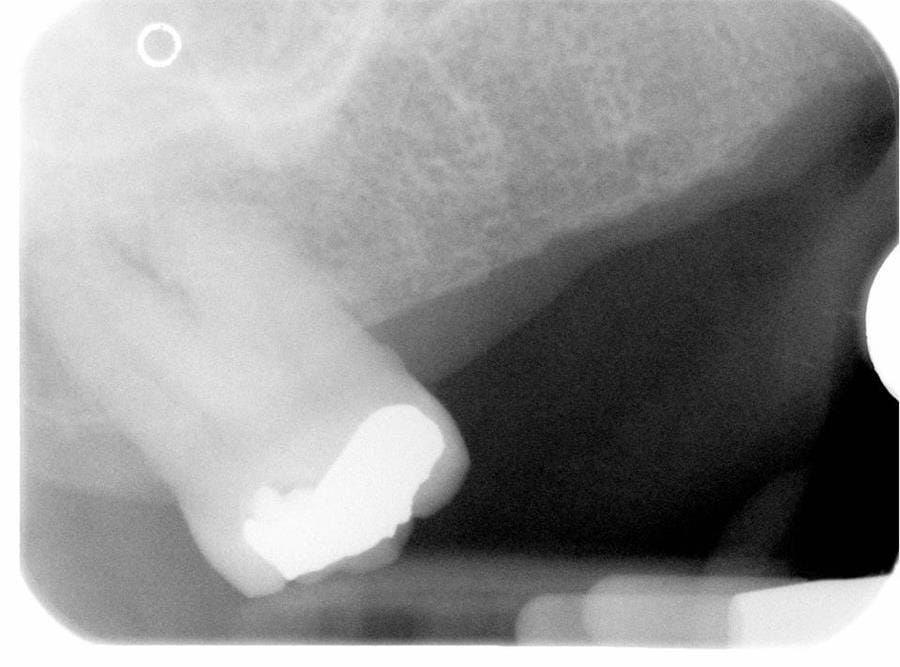

- UR7 - occlusal amalgam. 10- 20% alveolar bone loss. Healthy periodontium with reduced attachment level. No mobility.